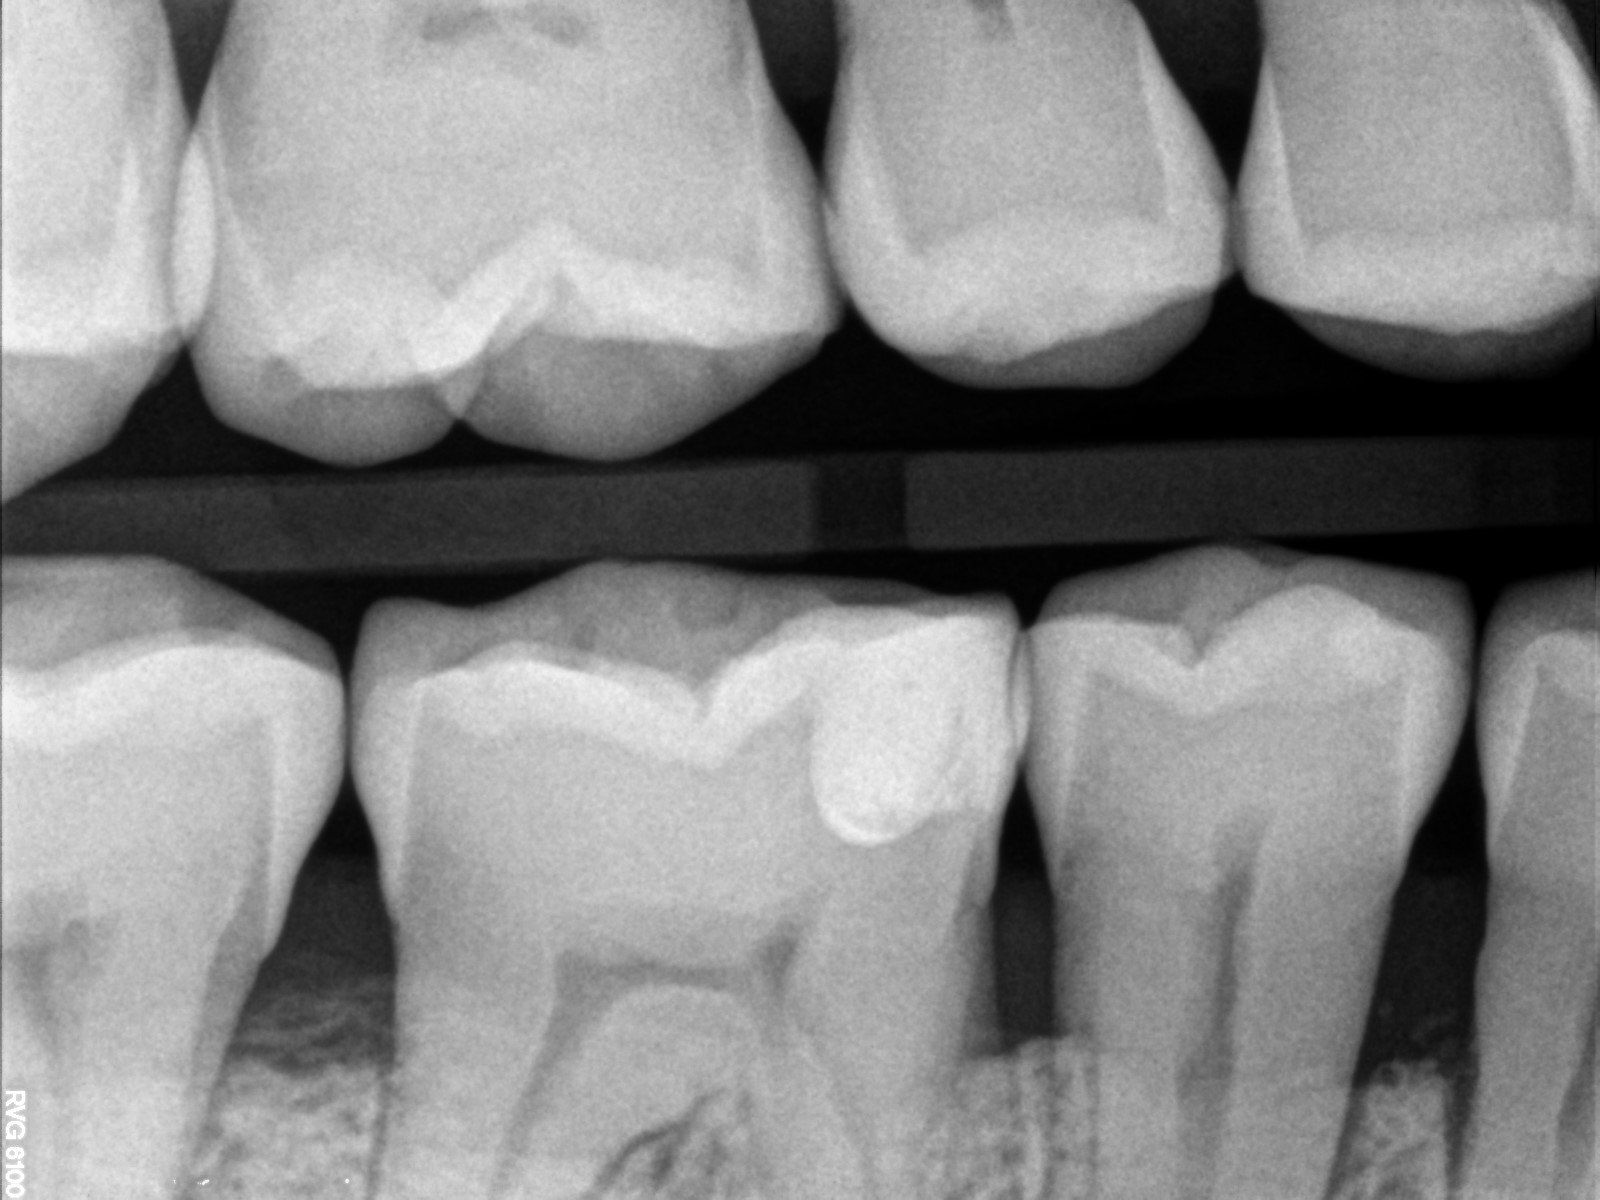

Endodonzia

Tra le mie competenze ci sono quelle specifiche per il settore dell’endodonzia.

Si tratta di una branca dell'odontoiatria che ha come principale obiettivo quello di procedere alla terapia di patologie che colpiscono l'endodonto ossia quello spazio presente all'interno dell'elemento dentario.

L'endodonzia è importantissima perché consente di prevenire ed eliminare dolori poiché, nella polpa dentaria, son presenti vasi e terminazioni nervose.

(la terza e quarta radiografia illustrano la devitalizzazione del dente senza l'eliminazione della capsula esistente ma solo con perforazione e ricostruzione nel punto preciso su capsula esistente).